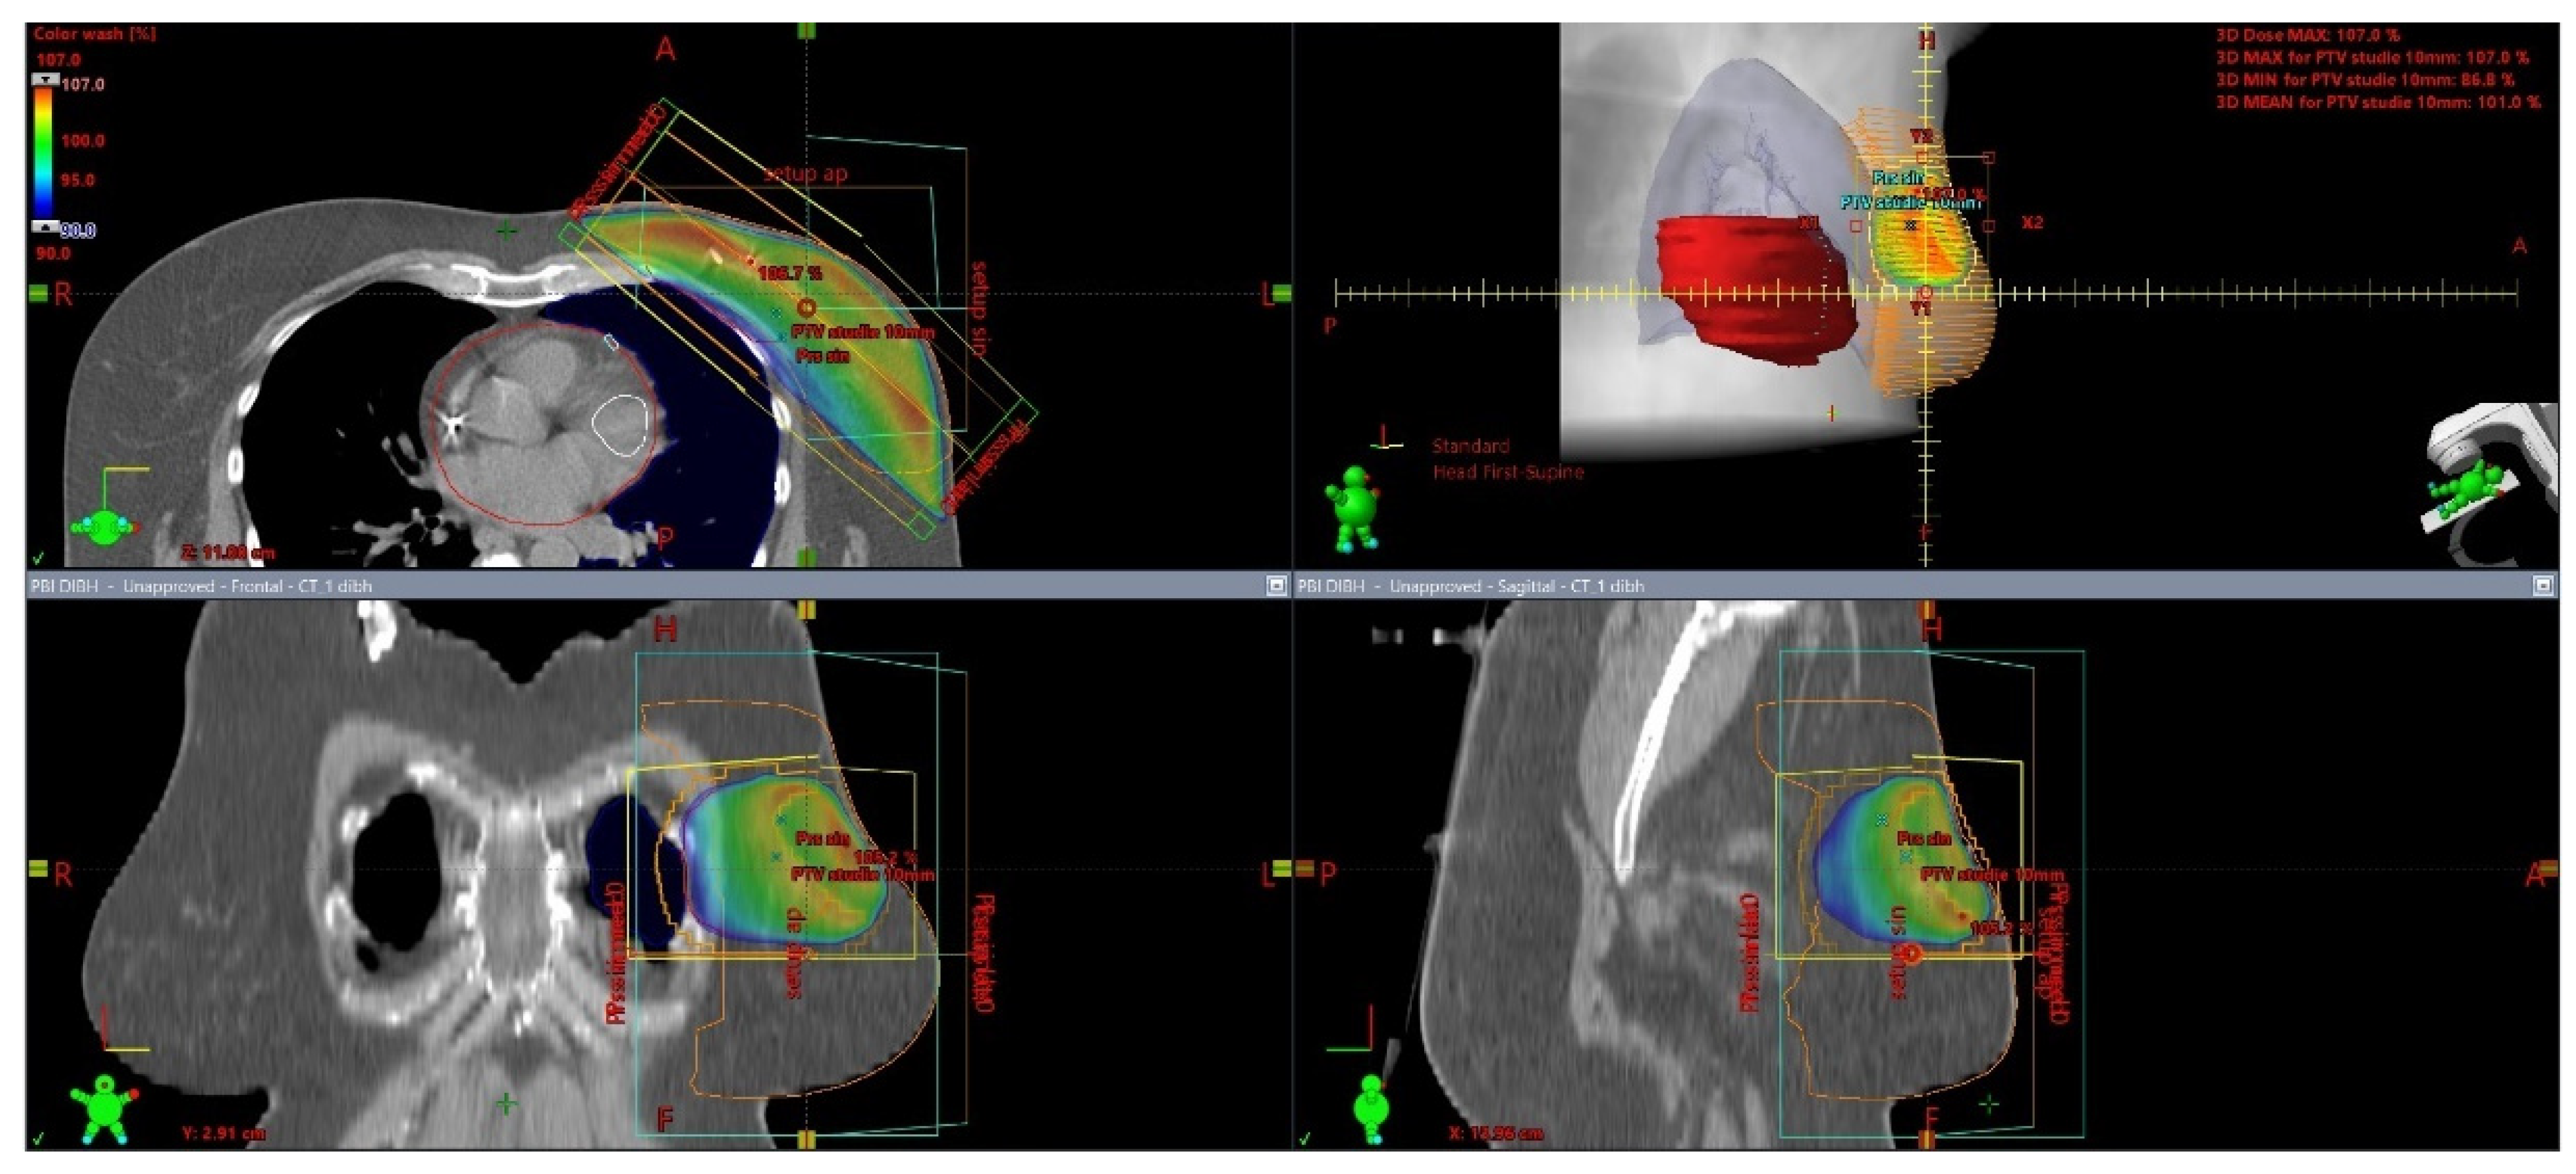

Figure 2.

3D visualization of external beam PBI technique from different viewing angles, delineation and dose distribution: heart—red, left ventricle and left anterior descending artery—white, left breast—orange, left lung—blue. Photon dose distribution produced by LINAC is presented by the color distribution: 95—107% of prescribed dose; 40 Gy/15 fractions.